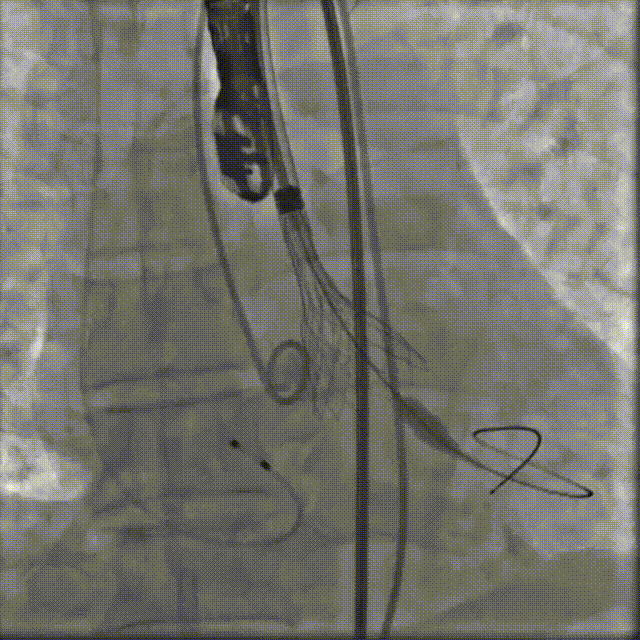

TaurusElite AV26瓣膜轻松过弓跨瓣,瓣膜初始定位瓣环0位,120bpm起搏下精准释放,释放到工作位后造影显示锚定充足,位置良好,冠脉未见遮挡,继续完成释放。

瓣膜初始定位

瓣膜释放过程

瓣膜释放后造影观察,根据影像判断反流较多,选择23mm球囊进行后扩。球囊后扩后反流量减少,瓣膜形态佳。

瓣膜脱钩

工球囊后扩